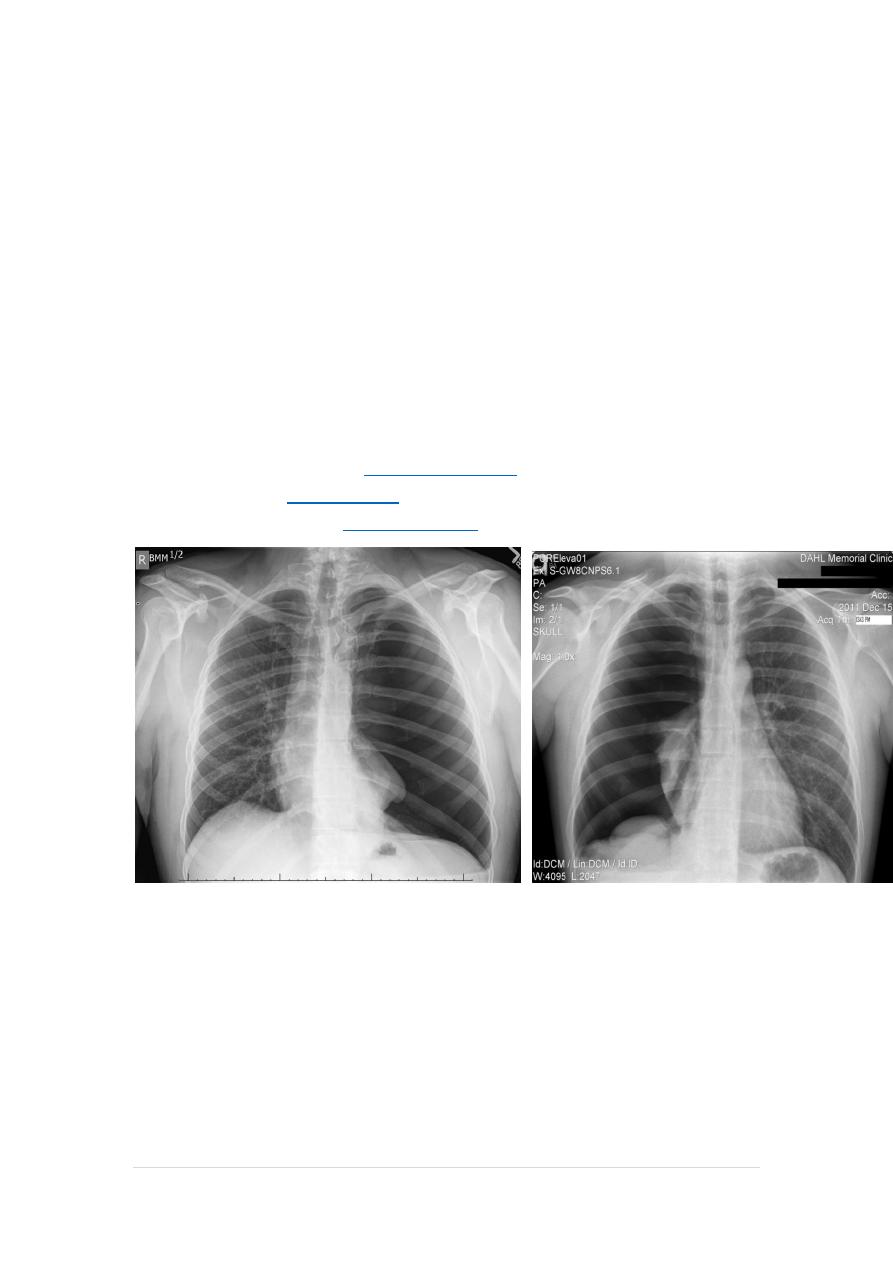

CXR (erect)

Both PA and AP erect films are insensitive to small amounts of fluid.

Features include:

blunting of the costophrenic angle

blunting of the cardiophrenic angle

fluid within the horizontal or oblique fissures

eventually a meniscus will be seen, on frontal films seen laterally and

gently sloping medially

with large volume effusions, mediastinal shift occurs away from the

effusion (note: if coexistent collapse dominates then mediastinal shift

may occur towards the effusion)